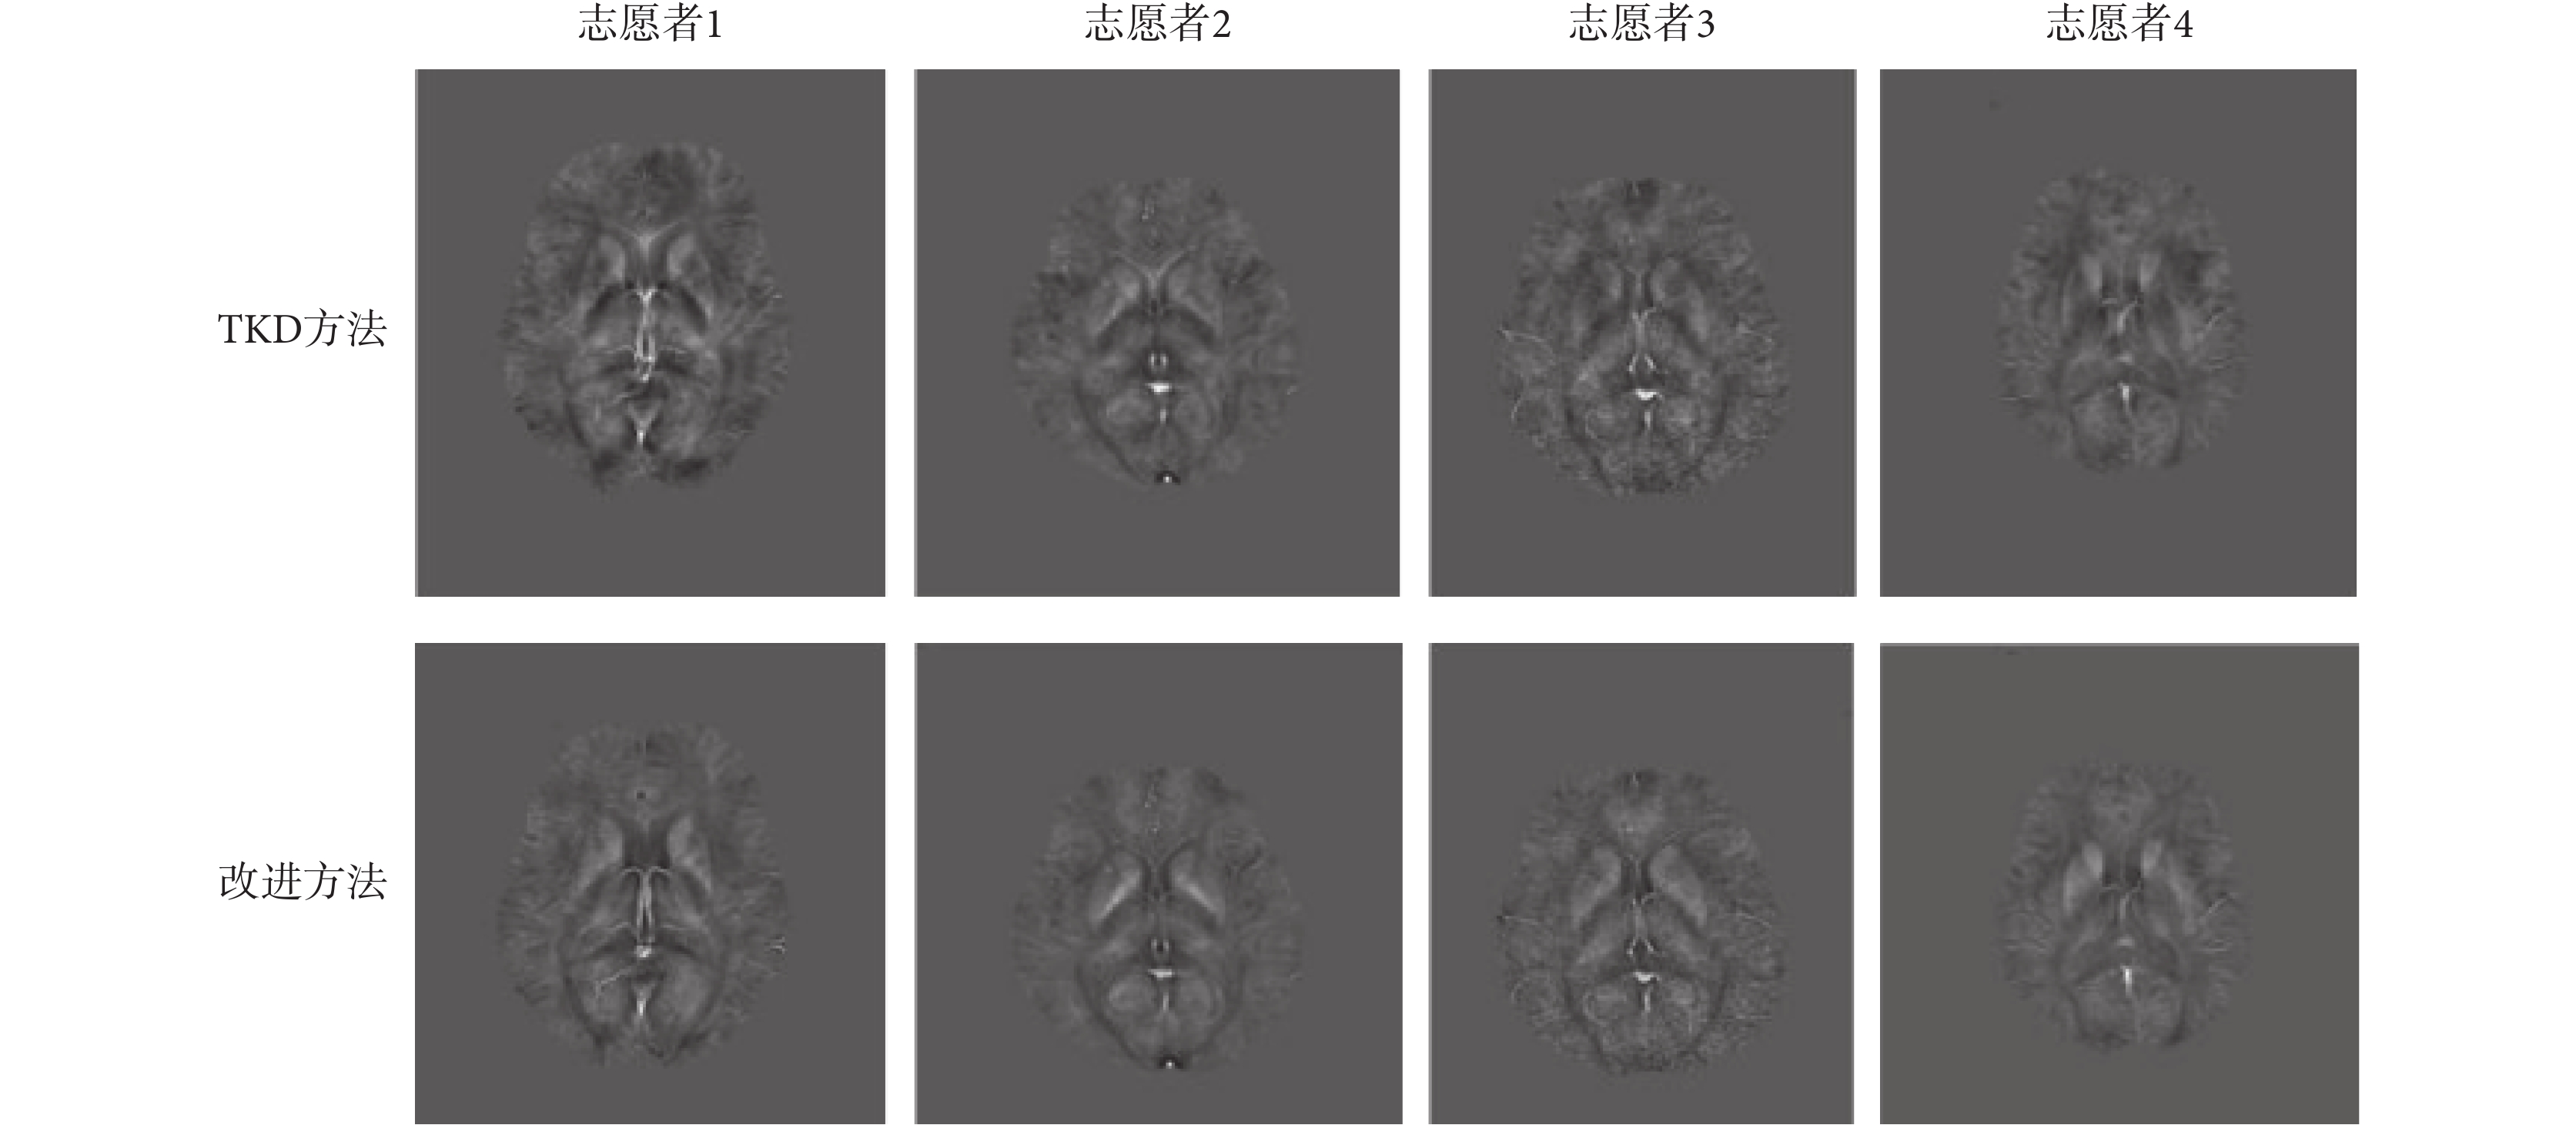

為了準確且直觀地評價兩種反演方法的重建結果,本文采集了多名志愿者的腦部數據,并對腦部多個感興趣區域的磁化率統計結果進行了分析。如圖 6 所示,是另外 4 名志愿者 TKD 方法及其改進方法的反演圖像,其中第一行的 4 幅圖像來自 4 名志愿者的 TKD 方法的反演結果,第二行是改進方法的反演結果。

從圖 6 的反演結果可以看出,改進方法的偽影明顯輕于原始方法,這與圖 5 得出的結論一致。如圖 7 所示,是磁化率與腦部鐵濃度的相關性分析,展示的是原始方法和改進方法反演的磁化率與腦部鐵濃度的相關性擬合直線。根據圖 7 的相關性分析得出初步結論,改進方法的磁化率與鐵濃度的相關性(R=0.874 2,P=0.019 7)低于原始方法的相關性(R=0.921 8,P=0.014 6),這說明改進方法的磁化率反演精度不如原始方法。但是,改進方法對偽影的抑制效果明顯優于原始方法,理論上偽影區域磁化率反演的精確性應高于原始方法,因此實驗選擇了 GP 和 DN 兩處偽影區域的磁化率統計結果替換到原始 TKD 方法的反演結果中,對融合后的磁化率與鐵濃度的相關性進行了分析,擬合直線以及相關系數如圖 7 中第三幅圖所示。由圖 7 可知,融合結果的磁化率與鐵濃度的相關性(R=0.979 6,P=0.007 1)高于原始 TKD 方法(R=0.921 8,P=0.014 6),這表明融合結果的磁化率與腦鐵濃度相關性較好,進一步說明偽影減輕區域的磁化率測量結果更加接近真實值。